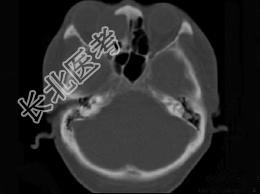

- 多项选择题女性38岁,右侧眼球运动障碍伴眼球突出4个多月, CT扫描如图,请选择正确的描述和答案 ( )

A、右侧筛窦内可见囊性肿块影,边缘光整

B、囊性肿块向右侧眼眶内突入,压迫内直肌

C、右侧眶内壁呈受压变薄、断裂

D、考虑为右侧筛窦黏液囊肿

E、考虑为筛窦癌